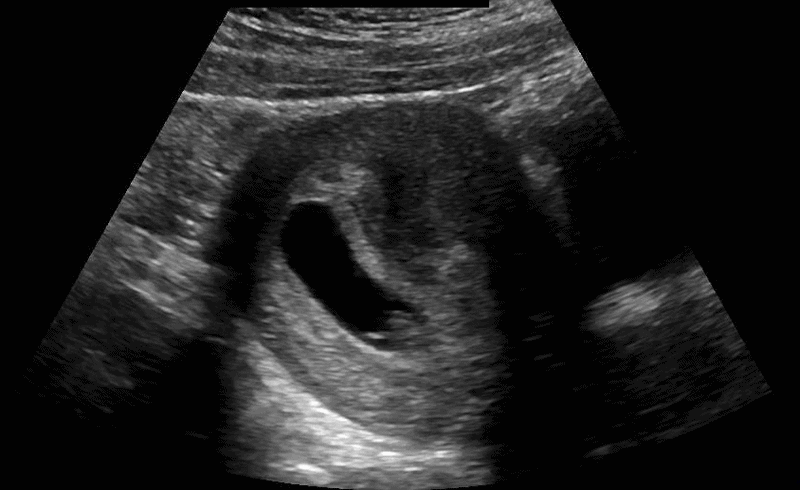

Scanning technique: When evaluating for intussusception with point-of-care ultrasound (POCUS), the infant is placed supine and a high-frequency linear transducer is used initially, with a curvilinear probe available for deeper or larger fields of view. The abdomen is scanned systematically in transverse and longitudinal planes, starting in the right lower quadrant and sweeping through the right upper quadrant, epigastrium, and left abdomen, with particular attention to the periumbilical region and right upper quadrant, where intussusception is most commonly identified. Graded compression is applied to displace bowel gas and improve visualization. On POCUS, intussusception classically appears as a “target” or “donut” sign in the transverse view, characterized by concentric hypoechoic and hyperechoic rings, and as a “pseudokidney” or “sandwich” sign in the longitudinal view. Associated findings may include proximal bowel dilation, free fluid, or absent peristalsis within the involved segment.

Image 1: Intussusception short axis diameter measurements.